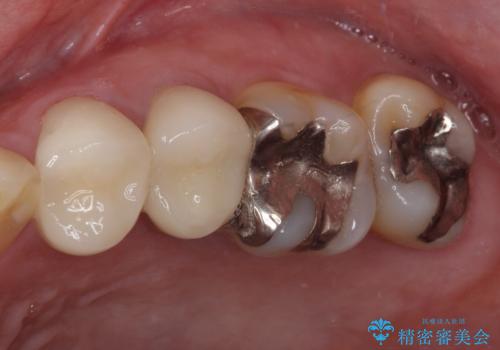

- 右下の欠損部の治療を希望して来院された患者様です。

部分矯正を行った後にインプラント埋入と手前の歯の根管治療を行い、その後補綴治療を行うこととしました。

治療途中より、上の歯や反対側の銀歯、上顎前歯の色合いや下顎前歯のデコボコが気になってきたため、全てを治療することとしました。